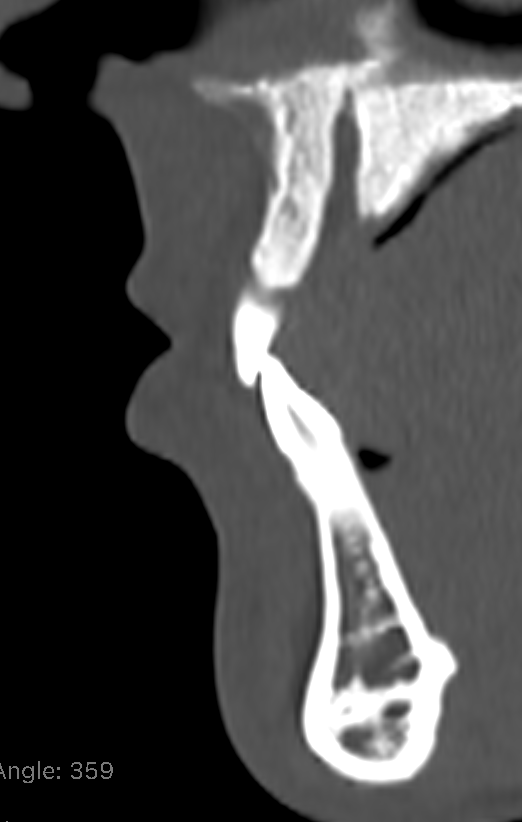

this is my pre op incissor position

is the lower lip bulging out because of teeth or just soft tissue?